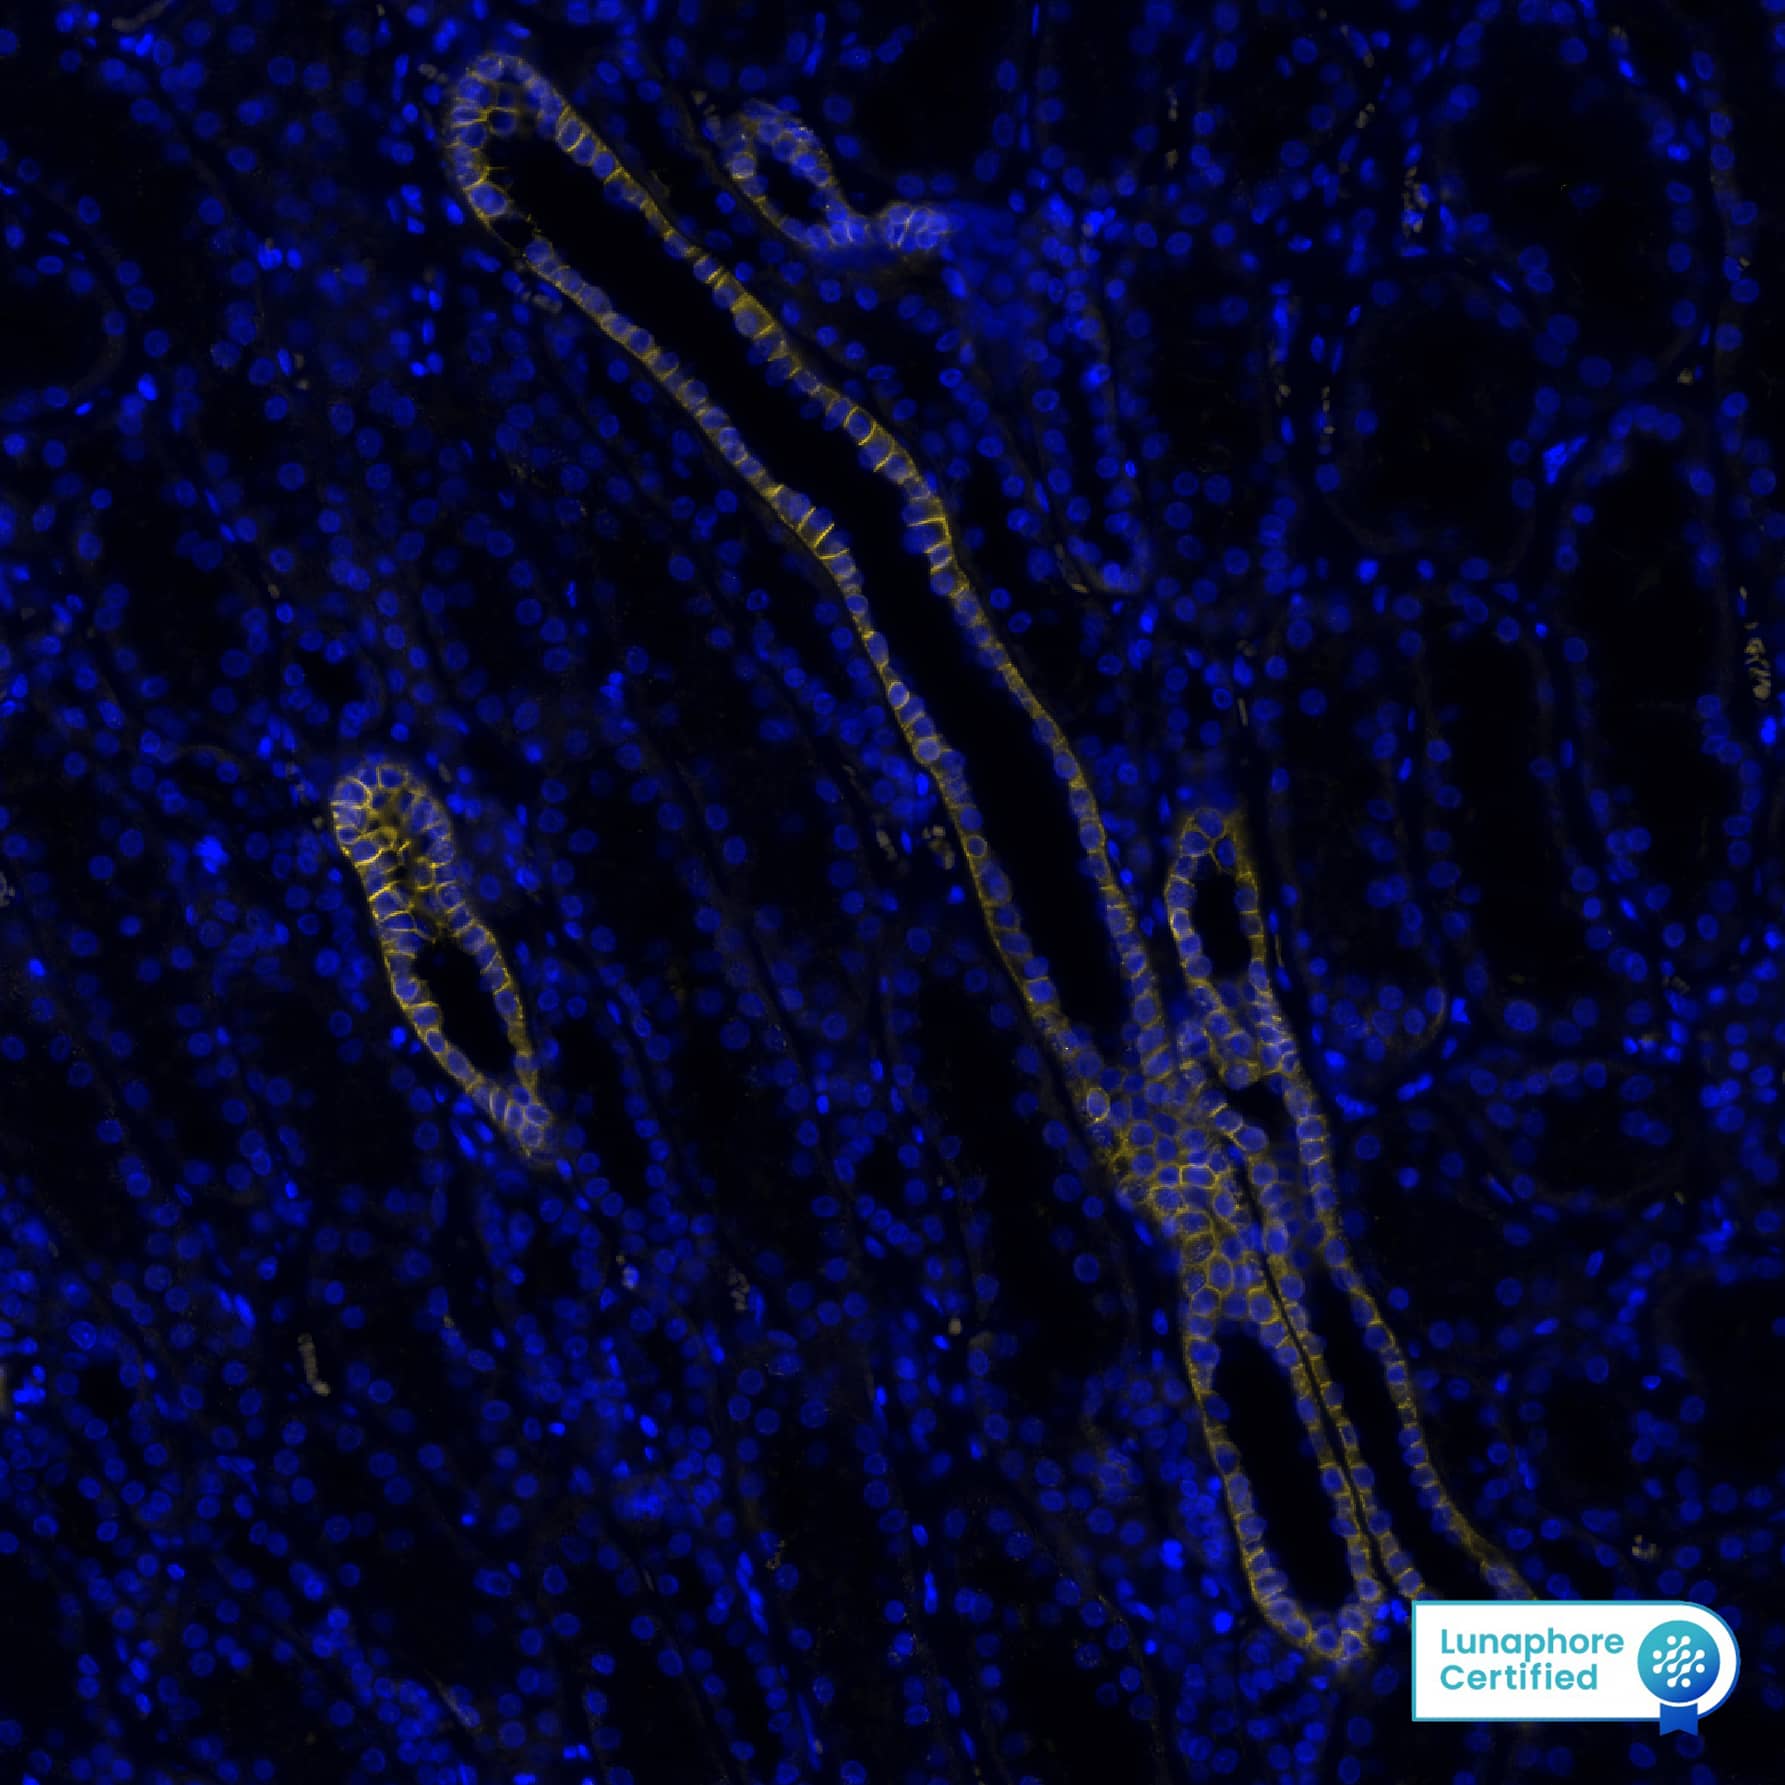

Detection of EpCAM/TROP-1 in Human Colon via Multiplex Immunofluorescence staining on COMET™

EpCAM/TROP-1 was detected in immersion fixed paraffin-embedded sections of human colon using Mouse Anti-Human EpCAM/TROP-1 Monoclonal Antibody (MAB960) at 1µg/mL​ at 37 ° Celsius for 4 minutes. Before incubation with the primary antibody, tissue underwent an all-in-one dewaxing and antigen retrieval preprocessing using PreTreatment Module (PT Module) and Dewax and HIER Buffer H (pH 9). Tissue was stained using the Alexa Fluor™ 647 Goat anti-Mouse IgG Secondary Antibody at 1:200 at 37 ° Celsius for 2 minutes. (Yellow; Lunaphore Catalog # DR647MS) and counterstained with DAPI (blue; Lunaphore Catalog # DR100). Specific staining was localized to the membrane. Protocol available in COMET™ Panel Builder.